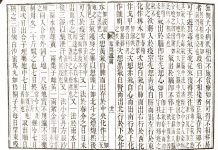

前回に続き腹證奇覧に記載されております、

小柴胡湯についてです。

胸脇苦満ノ毒、浅薄ナル者ノ圖也。

按之而知ノ傳、圖ノ如ク、

脇下肋骨ノ端ヲ指ニテカヽゲミルニ、コタユルモノアリ。

是薄キ苦満ノ毒ナリ。

又、心下ヲ按テ少シクコタユルモノナリ。

是即痞鞕ナリ。世二積聚ト号スルモノ、此ノ證多シ。

凡腹症ヲ按スル二、

毒ノ所在①厚深ナルモノハ見易ク、

②浅薄ナルモノハ見難シ。

然レドモ又③毒浅薄ナルカ、如クニシテ、大二深キモノアリ。

是毒腹底二在テ、悉ク表二顕レザルモノナリ。

コレヲ攻ルトキハ、其毒動テ表二顕ル其時弥本剤ヲ投ジテ、

不止之ヲ攻レバ、

或ハ寒熱往来、或ハ鬱ヽトシテ心煩スルモノ、是方證相對シテ暝眩スルナリ。

甚シキモノハ、振ヽ戦慄シテ、却テ發熱汗出瘧状ノ如ク覺ユルモノ。

是病毒去ルノ時ナリ。必恐懼スベカラズ。益本剤ヲ用テ可ナリ。

又其外世二所謂疫症外邪ノ類、六氣ノ變二敗レ出タルモノハ、

藥ヲ用ヒザル初ヨリ、件ノ外症ナド、様ヽ二顕ハスモノアリ。

右ノ診法ヲ詳ニシテ、胸脇苦満セバ、カマハズ此方ヲ投ズベシ。

外症二眩シテ、妄二方ヲ轉ズルコトナカレ。

又圖ノ如ク、苦満アリテ、心下痞硬甚シキモノアリ。

此時ハマヅ苦満ヲサシ置テ、痞鞕ヨリ攻ベシ。

人参湯、桂枝人参湯ノ類、證ヲ詳ニシテコレヲ用ユベシ。

是ノミニ限ラズ、病人諸症アラバ、マヅ其甚シキモノヨリ攻ベシ。

若甚シキモノナキ時ハ、上ヨリ順二攻ベシ。

妄二合方加減シテ、方法ヲ(阝+攵(かい))易スベカラズ。

必功ナキノミナラズ、却テ其害多カルベシ。

戒之戒之。

凡此症大率心煩アルモノナリ。

即柴胡或ハ人参ノ心煩ナリ。兼用ハ三黄丸、

或ハ知足斎ノ解毒丸等、可考用。